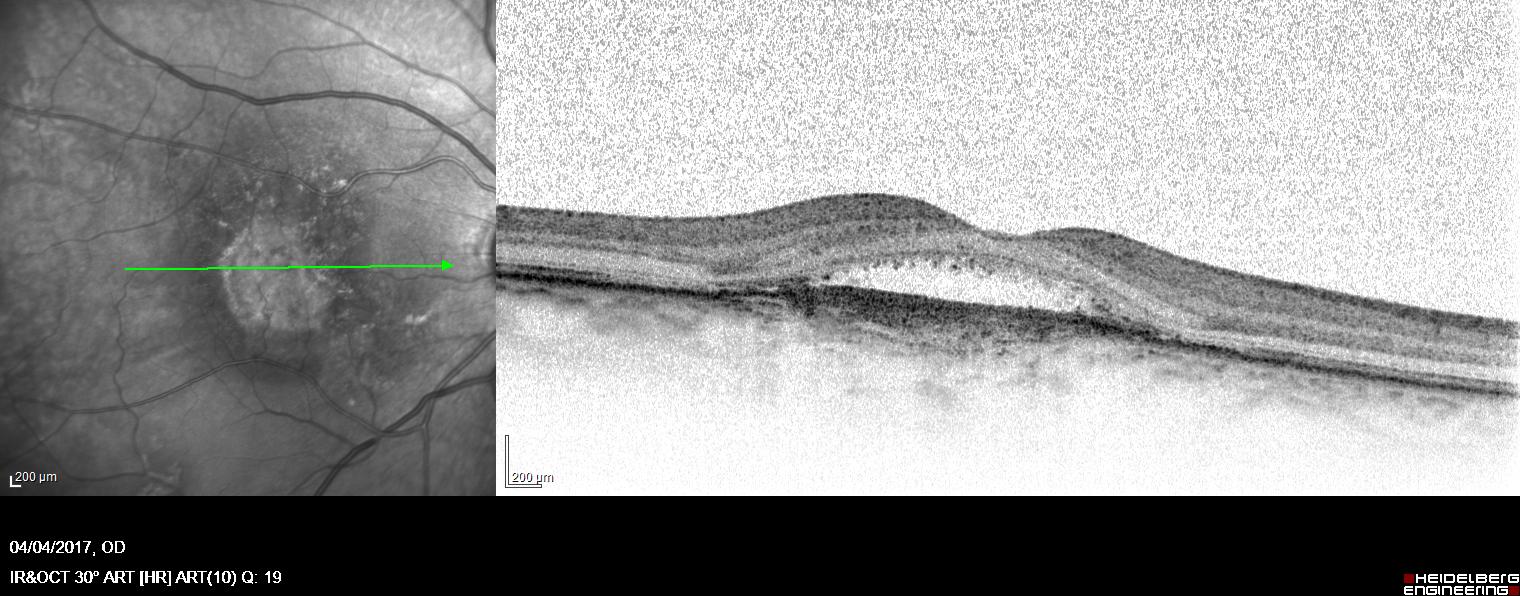

Oltre alle attività chirurgiche, il Dott. Acquaviva si avvale di tecnologie diagnostiche moderne per valutare in modo accurato lo stato di salute degli occhi. Esami come la tomografia a coerenza ottica (OCT), la pachimetria corneale e la misurazione del campo visivo sono strumenti fondamentali per un inquadramento completo e per la definizione del percorso terapeutico più efficace.